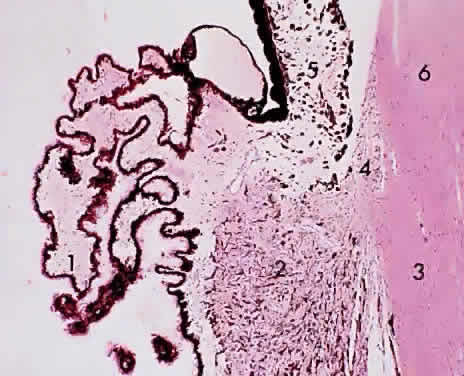

The ciliary body is triangular, 6 mm long, with its base abutting the root of the iris and the anterior chamber angle and its apex merging with the choroid and the ora serrata retinae. The ciliary body is commonly described in two sections, the anterior 2 mm (the pars plicata) and the posterior 4 mm (the pars plana). Therefore, surgery on the pars plicata to reduce aqueous secretion should be centered 2 to 3 mm from the limbus, whereas vitreous surgery through the pars plana should be initiated 3.5 to6 mm from the limbus to avoid injury to the lens anteriorly and to the retina posteriorly.

The pars plicata features approximately 80 radially placed ridged fronds representing the ciliary processes or crests (Fig. 10). The ciliary processes begin at the posterior border of the iris root and protrude into the posterior chamber. The processes have a vascularized connective tissue core covered by two layers of epithelium: a surface, nonpigmented, “secretory” cuboidal epithelium and an underlying pigmented epithelium layer (Figs. 11 and 12). The pigmented epithelial cells and the nonpigmented epithelial cells of the ciliary body are arranged apex to apex. The basement membrane of the pigmented epithelium faces the ciliary body stroma, whereas the basement membrane of the nonpigmented epithelium (internal limiting membrane) lines the posterior chamber and faces the vitreous and lens. During secretion of aqueous, nutrients from the capillaries in the ciliary processes pass through the endothelium and the basement membrane into the stroma, through the basement membrane of the pigmented epithelium to the pigmented epithelial cell, to the nonpigmented epithelial cell, and finally through its basement membrane (which forms the internal limiting membrane of the ciliary process). Tight junctions between the pigmented and nonpigmented epithelial cells inhibit leakage of nutrients between the cells. Aqueous humor formation is induced by active “secretion” by the inner cell layer (probably associated with the endoplasmic reticulum and the Golgi apparatus). Zonulae occludentes adjacent to the apical borders of the nonpigmented epithelial cells fill the lateral intercellular spaces to preserve the blood-aqueous barrier of the ciliary body.

Fig. 10. Ciliary body/pars plicata: 1, ciliary process; 2, ciliary muscle (radial and circular); 3, sclera; 4, anterior chamber angle trabecula; 5, iris; 6, cornea (× 105, KEI 8982B).